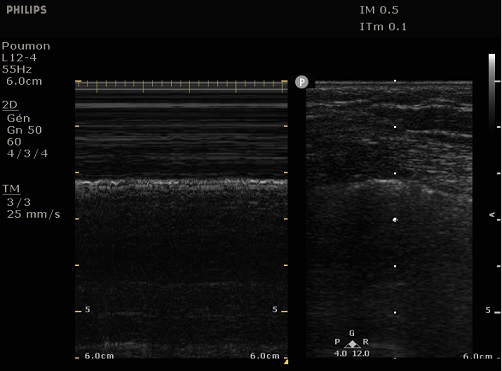

Normalement à mode T-M

echographique aspect de cote de mere est souvent en

presence |

En cas de pneumothorax sign de seashore

est disparue et on peut en vue aspect de code barre

sur les coupe echographi que mode T-M du thorax |

| |

|

Specialement dans le cas de epanchement

gazeux on peut en vue Point pulmonaire ( fleche noir

) : C'est

l'emplacement où l'image glissante du poumon

apparaît et disparaît soudainement ,

Le point ( fleche noire )

de differencie entre la zone pneumothorax ( barre

code ) et zone donc la plevre pảrietal et víceral

glissante ( cote de mere ). Ce point peut en s'observe dans pneumothorax enkyste , differencier le point entre zone affection ( pneumothorax ) et zone normale |